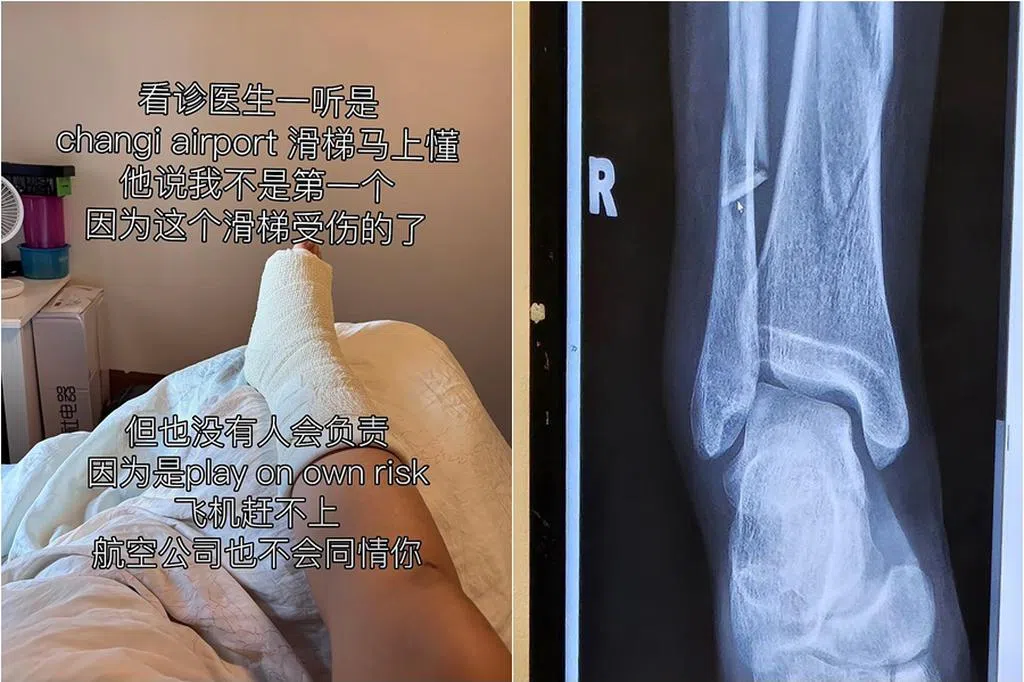

她指当天天气炎热,一家人选择就近的俱乐部用餐,随后她带着女儿到游泳池内玩耍。不料途中女儿突然说自己的脚很痛,她立刻抬起女儿的脚检查,赫然发现女儿脚趾血流不止。

Emillie立即从泳池上来,然后叫餐厅的员工上前帮忙止血。她称过程中只有一名服务员和厨师帮忙处理女儿的伤势,餐厅负责人并未上前询问或提供帮助。

她指餐厅安排医务人员来帮忙包扎止血,而医务人员说孩子伤口颇深,应尽快就医,结果孩子送院后伤口必须缝针。